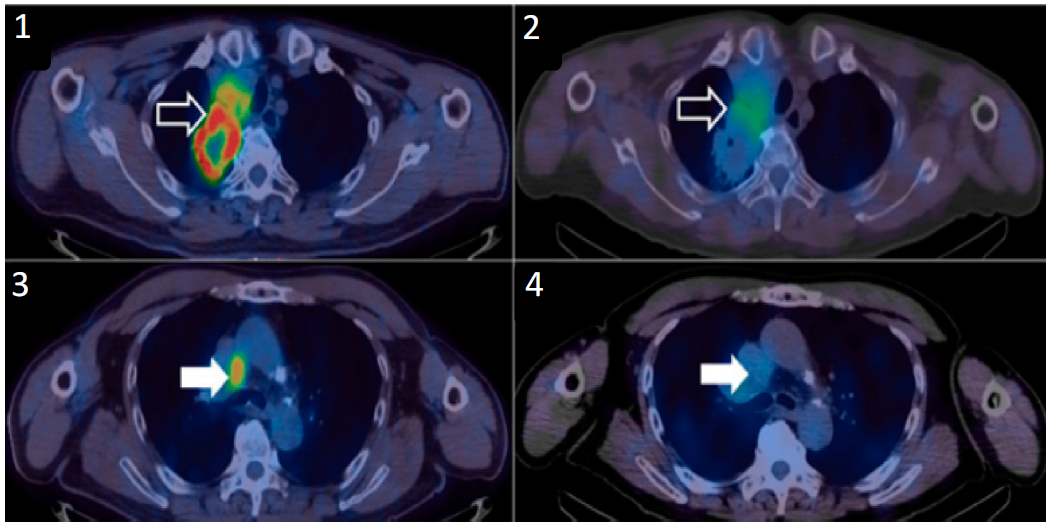

圖四、99mTc-NM-01在(NSCLC)患者中的成像數(shù)據(jù)?;颊叩挠疑戏稳~腫瘤顯示了高[18F]FDG攝取(1);以及高99mTc-NM-01攝?。?);縱隔淋巴結(jié)顯示了高[18F]FDG攝?。?);以及低99mTc-NM-01攝?。?);表明 PD-L1 在同一患者的原發(fā)腫瘤部位和遠(yuǎn)處疾病部位之間存在異質(zhì)性表達(dá)6。

99mTc-NM-01此前已在中國完成了早期一期臨床試驗(yàn)(NCT02978196)(圖四),評(píng)估了99mTc標(biāo)記的抗PD-L1納米抗體在非小細(xì)胞肺癌(NSCLC)中的安全性、劑量學(xué)和成像效果,與金標(biāo)準(zhǔn)——組織活檢相比,99mTc-NM-01成像結(jié)果具有良好的一致性,有可靠且非侵入性評(píng)估 PD-L1 表達(dá)的潛力。目前,該影像劑正在英國進(jìn)行新一輪的臨床試驗(yàn)(NCT04992715和NCT04436406),旨在評(píng)估99mTc-NM-01的診斷性能。